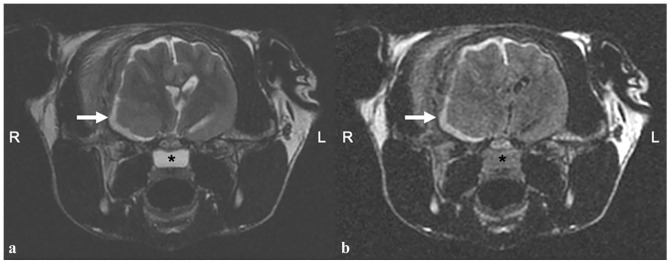

Case summary: A 4-year-old female neutered Scottish Fold shorthair cat was presented for further investigation of circling towards the right. MRI of the brain revealed an extensive, right-sided temporal muscle lesion with associated frontotemporal bone osteolysis, intracranial, extra-axial extension along the calvarial convexity with severe pachy- and leptomeningeal thickening and contrast enhancement, and an intra-axial space-occupying lesion in the right piriform lobe. The regional lymph nodes were moderately enlarged. Cytology of the right parotid lymph node and the temporal muscle was performed and histiocytic sarcoma (HS) was diagnosed. The owners elected euthanasia.

Relevance and novel information: HS of the central nervous system (CNS) is a very rare neoplastic condition in cats. Although a few case reports mention MRI, to our knowledge, the characterisation of MRI features of feline CNS HS have not been investigated in detail. Therefore, the aim of this case report was to describe the MRI characteristics in a feline HS involving not only the CNS, but also the fronto-temporal bone, temporal muscle and the regional lymph nodes. In particular, aggressive neoplastic bone invasion was a novel finding.